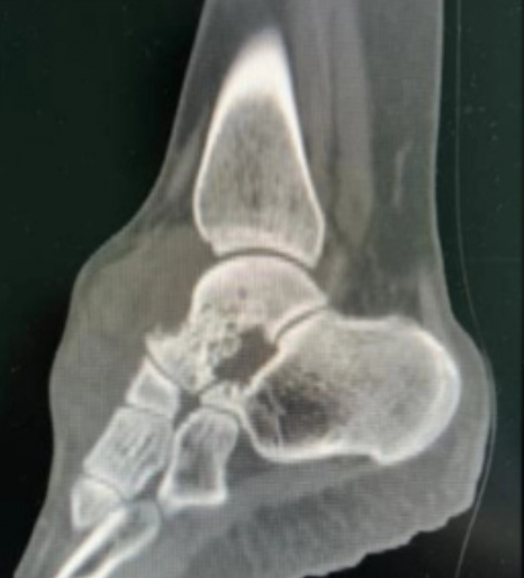

丽姐(化名)患足部腱鞘巨细胞瘤多年,已进行多次手术却又复发,并且肿瘤侵犯关节、累及关节面,严重影响了她的生活质量。

丽姐来到中国医学科学院肿瘤医院深圳医院骨科就诊时,肿瘤范围分布广泛,后确诊弥漫型腱鞘巨细胞瘤。